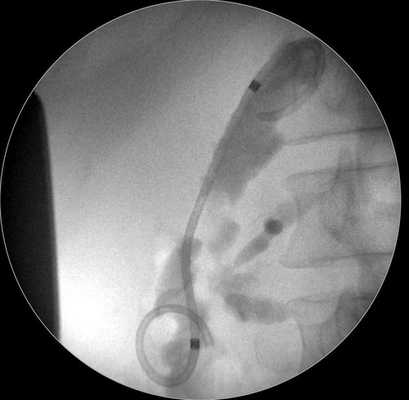

5. Установка трехлепесткового стента MTW таким образом, чтобы конец, содержащий два лепестка, оставался в просвете кисты (рис. 3, 4). Рис. 4. Эндоскопическая цистогастростомия с установкой в кисту трехлепесткового стента MTWE. Рис. 3. Эндоультразвуковое сканирование псевдокисты поджелудочной железы после цистотомии (в просвете определяется катетер) (пациент 1).

6. Альтернативный метод дренирования состоит в установке по металлическому проводнику, помещенному в полость кисты, наружного назобилиарного катетера, конец которого имеет форму pig-tail (рис. 5). Рис. 5. Наружное эндоскопическое дренирование с использованием назобилиарного катетера, конец которого имеет форму pig-tail (случай 2).

Затем под контролем рентгеноскопии в полость кисты вводится струна-проводник для установки пластикового стента (double pigtail) диаметром 10 Fr и длиной 10 см. Осуществляется рентгенологический и ультразвуковой контроль: он подтвердил, что дистальный конец стента располагается в просвете кисты, проксимальный - в луковице двенадцатиперстной кишки (рис. 5 в, рис. 6). При эндоскопическом осмотре оценивается область сформированного соустья для исключения кровотечения (рис. 7).